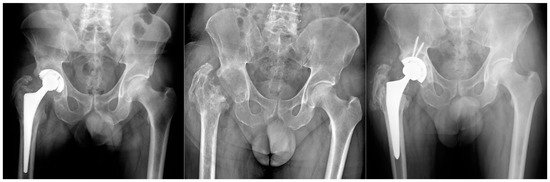

The same procedure was performed in all patients. Patients were explanted and antibiotic therapy was subsequently set up, at first empiric, and then targeted for the isolated pathogen. In no case were antibiotic spacers used. The antibiotic therapy was administered according to the culture sensitivity results. Antibiotic therapy was performed until normalization of CRP following explantation and, in any case, never for more than 8 consecutive weeks. One year after resection arthroplasty was performed, the following two possible outcomes were evaluated: successful TSE arthroplasty was performed in 14 patients (Group A) (Figure 1), and resection arthroplasty without reimplantation in 7 (Group B) (Figure 2). The following were the replanting criteria: CRP normalization with antimicrobial treatment in at least two controls separated by two weeks. If normalized, antibiotic therapy was discontinued, patients were then monitored for an additional 4 weeks by weekly CRP checks. If the latter remained normal, labeled leukocyte scintigraphy was done. If the latter was also negative, reimplantation was scheduled, which was to be performed only after intraoperative negative histology.

Figure 1.

Group A Patient affected by chronic PJI treated with TSE. The patient was eligible for reimplantation after 4 month targeted antimicrobial therapy. After 12 months follow up there were no signs of recurrence of infection.

Figure 2.

Group B. Patient with communicating sinus tract at the diagnosis. After ex-plantation and targeted antimicrobial therapy for a polymicrobial PJI, the patient was not considered eligible for reimplantation.